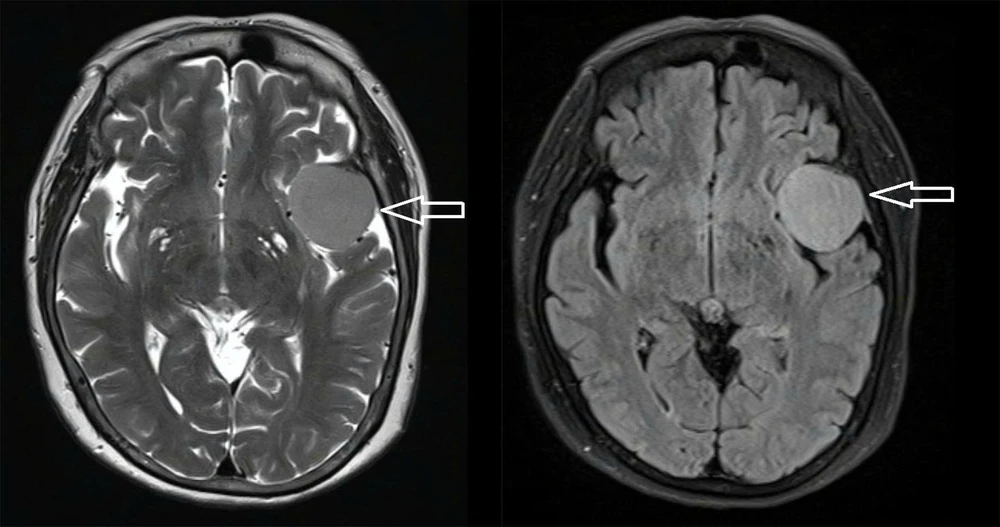

Bệnh nhân nhập viện trong tình trạng đau đầu kéo dài và từng điều trị giảm đau thông thường nhưng không hiệu quả. Sau một lần té ngã trong lúc tắm, bệnh nhân được gia đình đưa đến bệnh viện, qua CT và MRI phát hiện khối u màng não ở vị trí sàn sọ phức tạp, cần phẫu thuật.

Khối u trước phẫu thuật của cụ bà 73 tuổi. Ảnh: BVCC

Theo các bác sĩ, khó khăn của ca bệnh này là bệnh nhân có nhiều bệnh nền như tăng huyết áp, đái tháo đường type 2, tim thiếu máu cục bộ. Trước mổ, ê-kip phải phối hợp chặt chẽ với chuyên khoa nội tiết và tim mạch để kiểm soát tình trạng, đồng thời ngưng thuốc chống đông 5 ngày.

Ca phẫu thuật kéo dài, màng cứng dày dính vào hộp sọ, nhưng ê-kip đã đạt kết quả Simpson I (lấy trọn u). Sau mổ, bệnh nhân được an thần sâu 48 giờ, hồi phục dần và đến ngày 4/9 đã tỉnh táo, nói chuyện tốt, được chuyển về khoa Ngoại thần kinh tiếp tục điều trị.